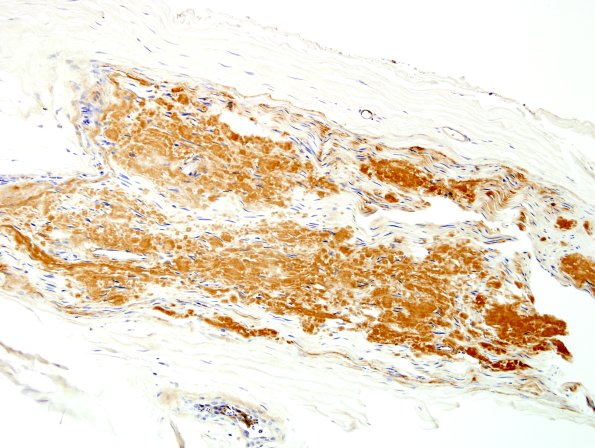

19A4 Amyloid NP (Case 19) Anti-Kappa 7

Endoneurial masses of kappa light chain immunoglobulin. (kappa IHC)